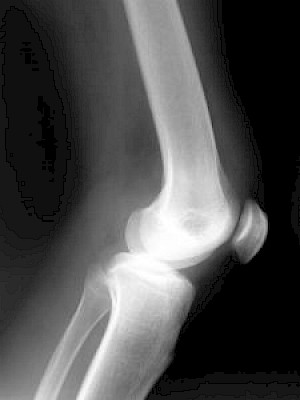

Knieschmerzen

Folgende Fallunterscheidungen sollten bei Knieschmerzen getroffen werden: